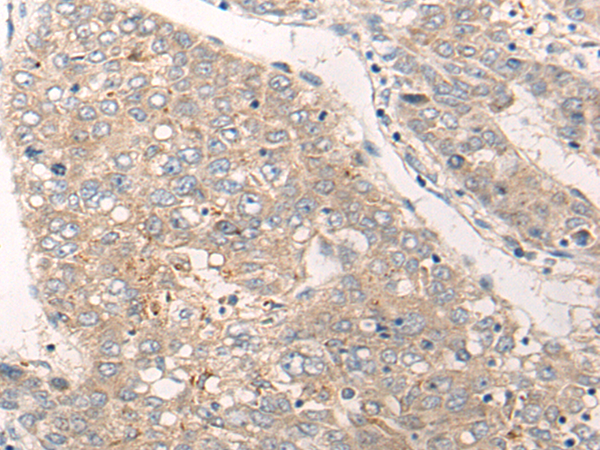

IHC positive control: |

Human liver cancer |

IHC Recommend dilution: |

20-100 |